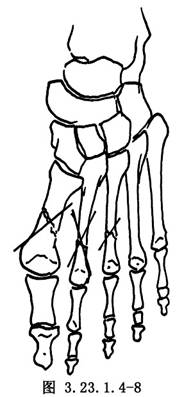

2.将两骨折段准确复位,用克氏针做斜行或交叉固定,克氏针要穿过近、远段的骨皮质,剪除过多的钢针,针尾留在皮下(图3.23.1.4-8)。